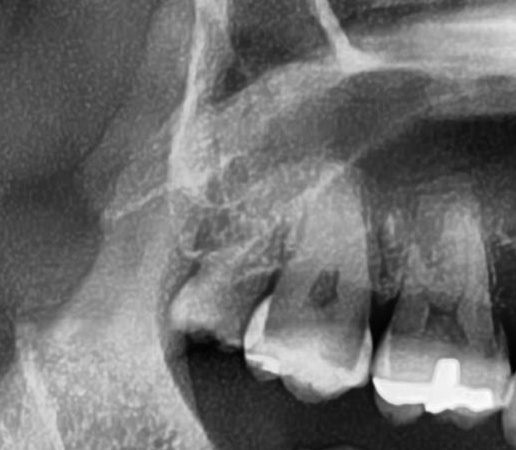

次にパノラマ写真を撮影してみると、右上の親知らずは手前の歯と並んでまっすぐ生えているのが確認できました。

今回は上顎洞からも距離があるため、抜歯は可能と診断されました。